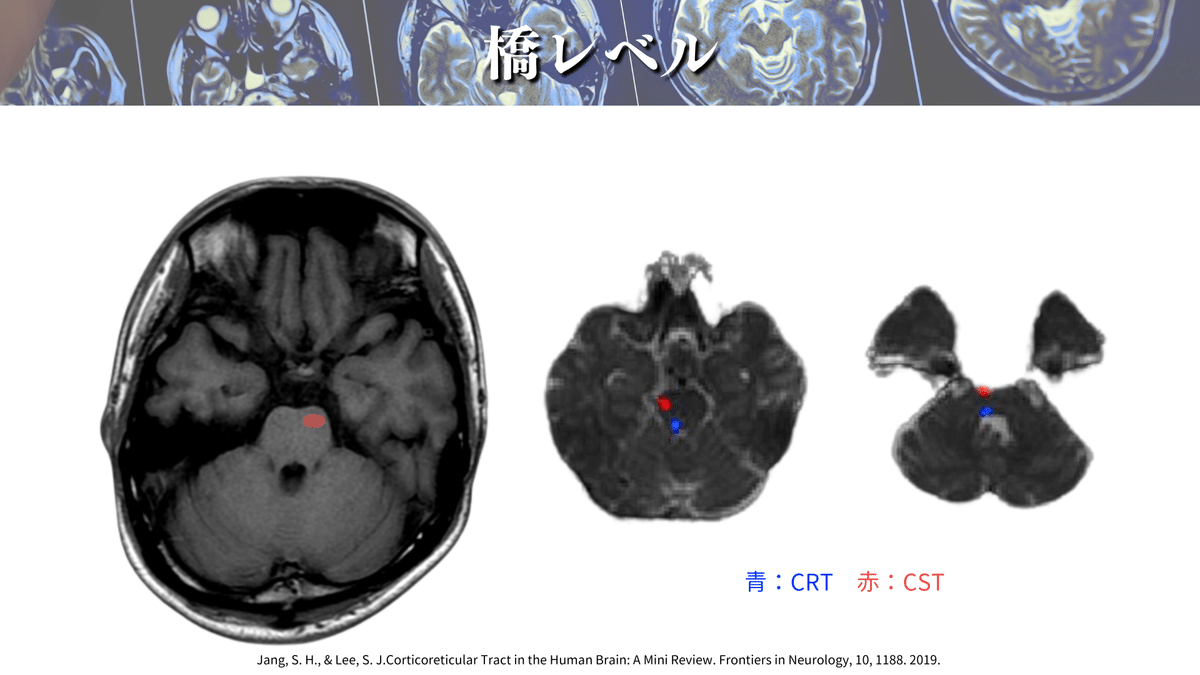

橋レベル

では、さっそく解像度を上げた画像を見てみましょう🔍

CSTは前方(橋底部)を通過しているのが分かりますね👀

橋のレベルは他の脳幹とは少し性質が異なり、右図のようにCSTが分散します!

話を脳画像読影に戻しまして、、、

DTTで確認してみると、橋底部をCSTが通過していることが分かりますね!

橋では主に前方(橋底部)を走行すると覚えるといいかもしれませんね☝️